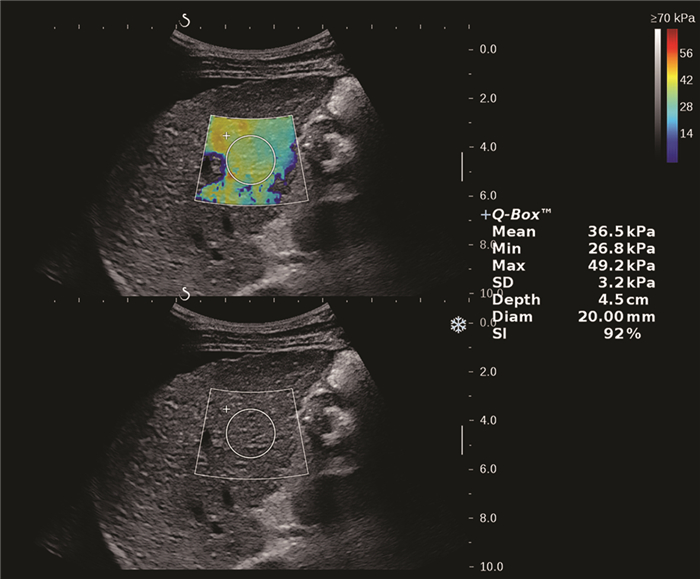

Clinical value of two-dimensional shear wave elastography in predicting esophageal varices in patients with hepatitis B cirrhosis by evaluating liver and spleen stiffness

Xuemei WANG, Yao ZHANG, Xueping YANG, Yue WANG, Mixue WANG

2021, 37(5): 1081-1084. DOI: 10.3969/j.issn.1001-5256.2021.05.021

Abstract(1360) HTML (289) PDF (2305KB)(71)

Abstract:

Objective  To investigate the value of two-dimensional shear wave elastography (2D-SWE) in the noninvasive evaluation of the presence or absence of esophageal varices (EV) in patients with hepatitis B cirrhosis by liver stiffness measurement (LSM) and spleen stiffness measurement (SSM).  Methods  A total of 172 patients who were diagnosed with hepatitis B cirrhosis in Beijing Ditan Hospital, Capital Medical University, from April 2019 to February 2020 were enrolled in a prospective study, and according to the results of gastroscopy, they were divided into non-EV group and EV group. The two groups were compared in terms of spleen thickness (ST), spleen diameter (SD), LSM, and SSM. The independent samples t-test was used for comparison of normally distributed continuous data between two groups, and the Mann-Whitney U test was used for comparison of non-normally distributed continuous data between two groups; the chi-square test was used for comparison of categorical data. The receiver operating characteristic (ROC) curve was used to investigate the value of LSM and SSM in the diagnosis of EV, and the Z test was used to compare the diagnostic accuracy of LSM and SSM.  Results  There were 121 patients in the EV group and 51 patients in the non-EV group. There were significant differences between the two groups in ST (t=8.143, P < 0.001), SD (t=7.363, P < 0.001), LSM (Z=3.024, P=0.002), SSM (t=15.142, P < 0.001), and presence or absence of ascites (χ2=22.101, P < 0.001). LSM had an area under the ROC curve (AUC) of 0.646 (95% confidence interval [CI]: 0.570-0.718) in the diagnosis of EV, with a sensitivity (Se) of 83.47%, a specificity (Sp) of 47.06%, a positive predictive value (PPV) of 78.9%, and a negative predictive value (NPV) of 54.5% at the optimal cut-off value of 13.16. SSM had an AUC of 0.951 (95% CI: 0.907-0.978) in the diagnosis of EV, with an Se of 80.99%, an Sp of 96.08%, a PPV of 98.0%, and an NPV of 68.1% at the optimal cut-off value of 38.08. SSM had a better diagnostic accuracy than LSM (Z=6.096, P < 0.001).  Conclusion  LSM and SSM can be used to predict the presence or absence of EV in patients with hepatitis B cirrhosis. SSM has a higher accuracy than LSM and can provide accurate diagnostic information for clinical practice.